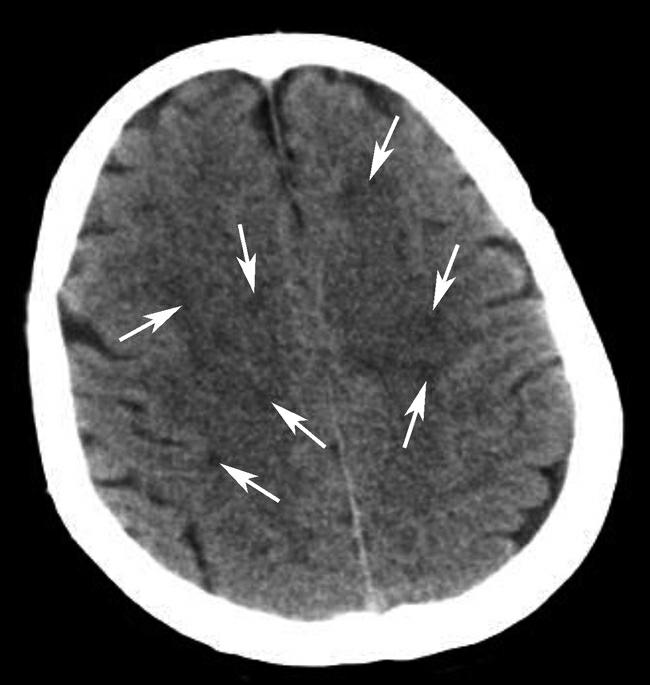

Alberta卒中项目早期CT评分(Alberta stroke program early CT score,ASPECTS)是一种评价急性缺血性卒中患者大脑中动脉供血区早期缺血性改变的简单、可靠、系统化的方法,是常用的脑卒中评定量表之一,可对缺血性病变快速进行半定量评价,有助于判定溶栓效果和远期预后。该评分主要基于CT平扫,具体分区如下(图1-2-76)所示,即选取大脑中动脉供血区2个层面。分区后共10个区域,每个区域记1分。评分时任何区域只要有低密度灶,则扣除该区域得分。正常脑ASPECTS评分为满分(10分),若MCA供血区广泛梗死累及全部区域时,则ASPECTS评分为0分。

图1-2-76 ASPECTS评分脑组织分区

A.在基底节层面(即丘脑和纹状体平面),分为各级分支M 1 、M 2 、M 3 、岛叶(缩写I)、豆状核(缩写L)、尾状核(缩写C)和内囊(缩写IC)后肢等7个区域;B.在基底节以上层面(基底节层面上2cm),包括M 4 、M 5 和M 6 。